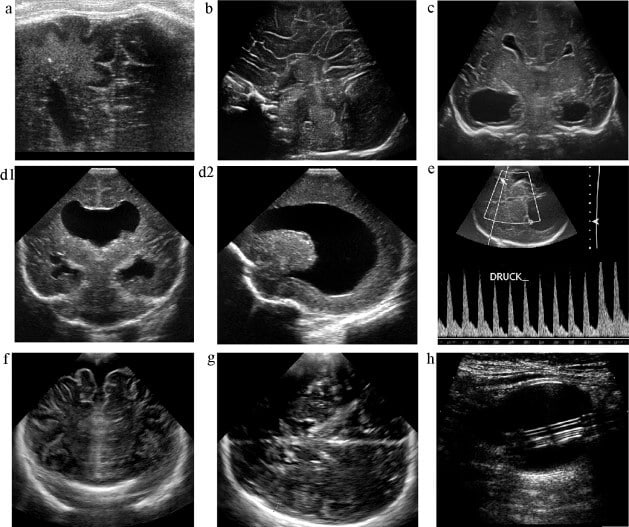

Quando restrito a área da vasculatura da matriz germinativa subependimária, denomina-se o sangramento como sangramento subependimário (SEB). Por outro lado, caso haja ruptura para o ventrículo lateral, forma-se a hemorragia intraventricular (HIV).

Nesse contexto, com base em sua extensão, divide-se as hemorragias intracranianas em quatro graus:

- I: sangramento restrito à matriz germinativa;

- II: extensão ao ventrículo sem dilatação;

- III: extensão ventricular com dilatação;

- IV: infarto hemorrágico periventricular.

Na ultrassonografia, essas hemorragias geralmente aparecem como áreas ecogênicas, sendo possível visualizar coágulos dentro dos ventrículos. Contudo, nos estágios iniciais, o sangue fresco pode não ser detectado facilmente, sendo perceptível apenas pelo movimento de partículas no líquido cefalorraquidiano, especialmente com Doppler colorido.

A evolução clínica é variável: pequenos sangramentos podem regredir espontaneamente, deixando cistos pós-hemorrágicos, enquanto hemorragias extensas podem levar a ventriculite asséptica, obstrução do fluxo liquórico e consequente hidrocefalia pós-hemorrágica. Além disso, como já mencionado, podem ocorrer infartos hemorrágicos periventriculares, que deixam como sequelas cistos porencefálicos ou áreas de glioses cicatriciais.

Além disso, o Doppler transcraniano é um recurso fundamental, permitindo avaliar a hemodinâmica cerebral. Inicialmente o fluxo pode ser normal, mas após a reperfusão surgem alterações como hiperemia, redução do índice resistivo (IR) e, em fases graves, diminuição ou inversão do fluxo diastólico, até a ausência de perfusão periférica compatível com morte cerebral.

Ademais, nos prematuros, destaca-se a leucomalácia periventricular (LPV), decorrente de hipóxia em regiões vulneráveis, que se manifesta por ecogenicidade periventricular irregular e assimétrica, evoluindo para formação de cistos e perda de substância branca.